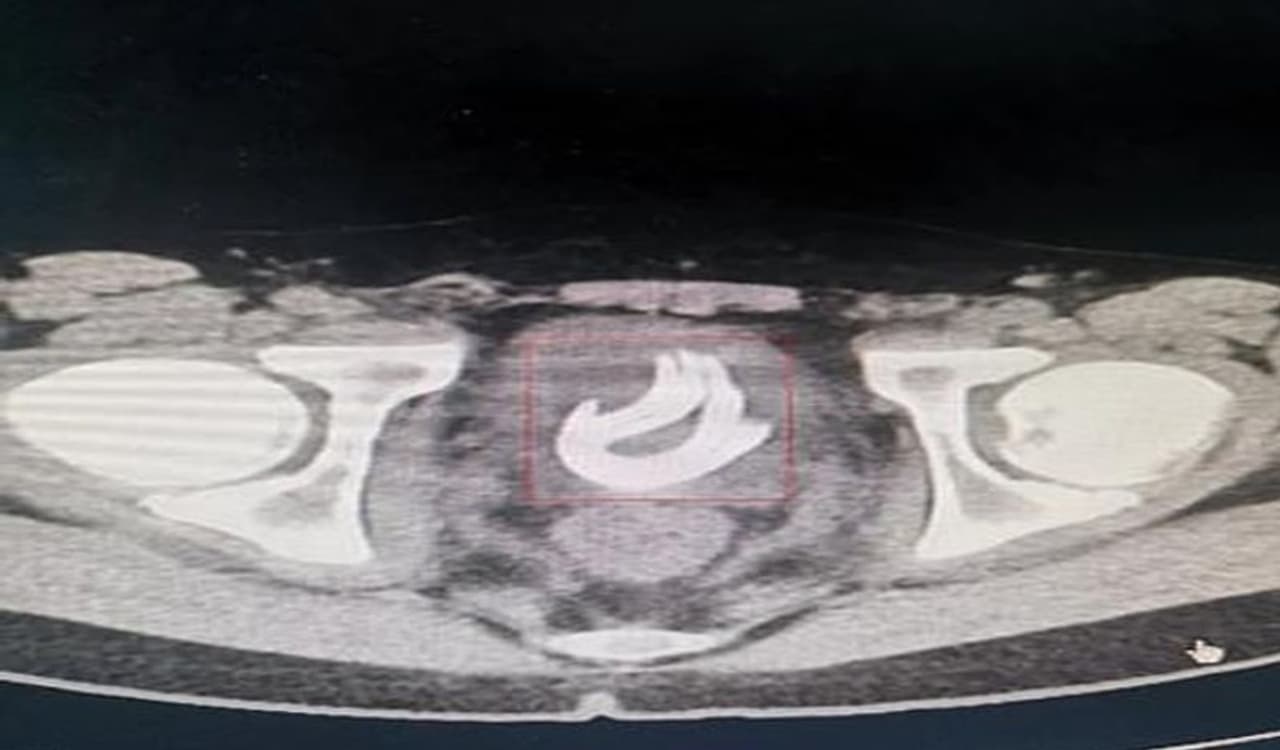

जब बच्चे की एक्सरे रिपोर्ट आई, तो सब हैरान रह गए। उन्होंने देखा कि बच्चे के ब्लेडर में दो फुट लंबी तार है। इसके तुरंत बाद बच्चे को एडमिट कर लिया गया।

डॉक्टर्स ने सर्जरी कर बच्चे के मूत्राशय से दो फुट की तार बाहर निकाली। जब बच्चे से इसके बारे में पूछा गया तो उसने बताया कि तीन महीने पहले उसने इस तार को प्राइवेट पार्ट के जरिये बॉडी में घुसाया था।

डॉक्टर्स ने सर्जरी के बाद बच्चे की जान बचा ली। उन्होंने कहा कि गनीमत है कि तार से बच्चे को कोई नुकसान नहीं पहुंचा। इस सर्जरी में घंटे का समय लगा। जिसके बाद 70 सेंटीमीटर लंबा तार बाहर निकाला गया।